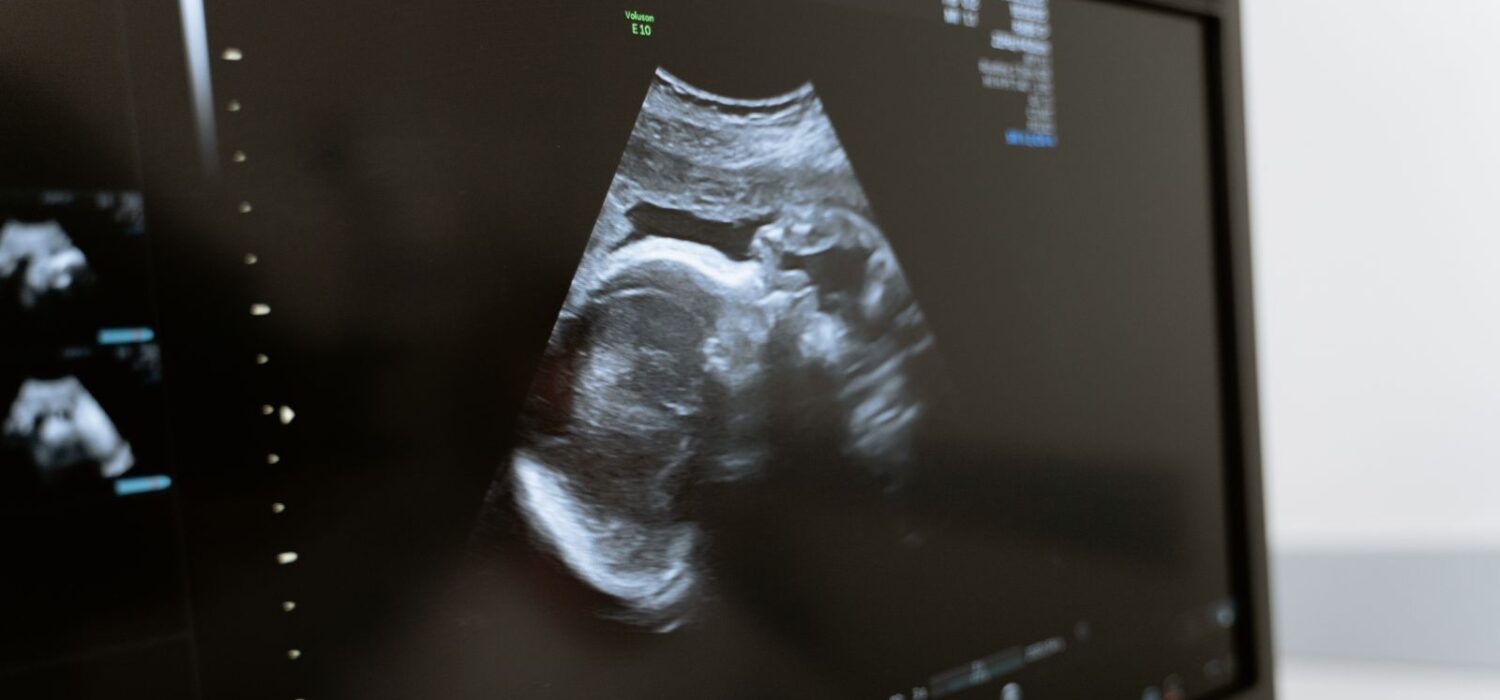

En las ecografías se ha visto que los bebés sonríen, fruncen el ceño y hacen gestos dentro del útero. También practican movimientos que fortalecen su coordinación, como patear o estirarse. Además, ya comienzan a familiarizarse con el ritmo y la melodía de tu idioma, lo que les facilita reconocerlo después del nacimiento.